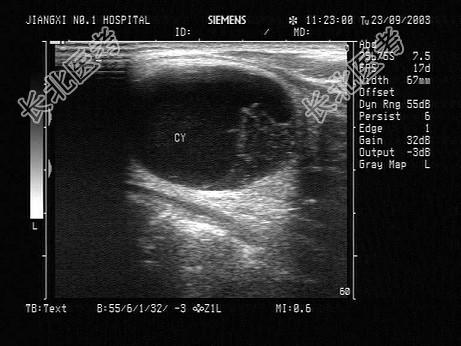

- 单项选择题患者,男性, 甲状腺一侧可触及包块,超声见边界清晰的低回声光团, 包膜完整。如图所示,最可能的诊断为 ( )

A、甲状腺囊肿

B、甲状腺腺瘤并囊性变

C、结节性甲状腺肿

D、甲状腺炎

E、甲状腺腺瘤